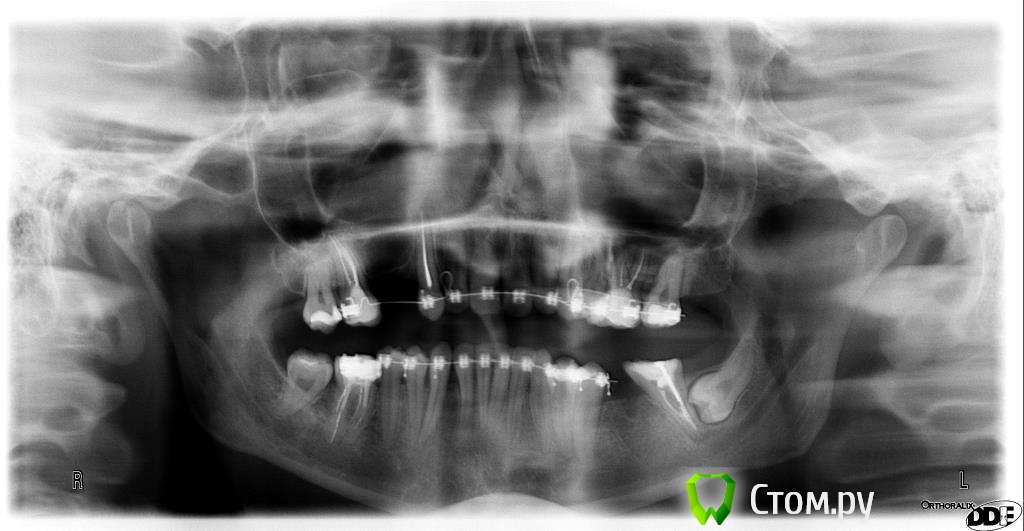

2,5 года прохожу ортодонтическое лечение на брекетах  системы Виктори ( металлических)., в последствии буду протезироваться на имплантах

Прилагаю все имеющиеся снимки ( до и сейчас) и фото данный момент.

1-в общем, есть вопросы по каналам депульпированных зубов

2-смущает окклюзионная плоскость на нижней челюсти.

3- 37-зуб возможно стоит "выпрямить более вертикально))"

4-Так же стоит обратить внимание на изменения в суставе, возможно стоит дообследоваться, опять же, по ОПТГ об этом не судят, но изменения есть, скорее всего это связано с отсутствием моляров. Проблемы с ассиметричным положением нижней челюсти решаться, с исправлением окклюзионнй плоскости, и восстановлением межальвеолярной высоты.

5-38 зуб- я бы рекомендовал убрать)

ортодонт говорит лечение закончено, пора  снимать.А нижние  и правда  асимметричны,это видно, но она  ничего не делала

это же  брекетами исправляется?